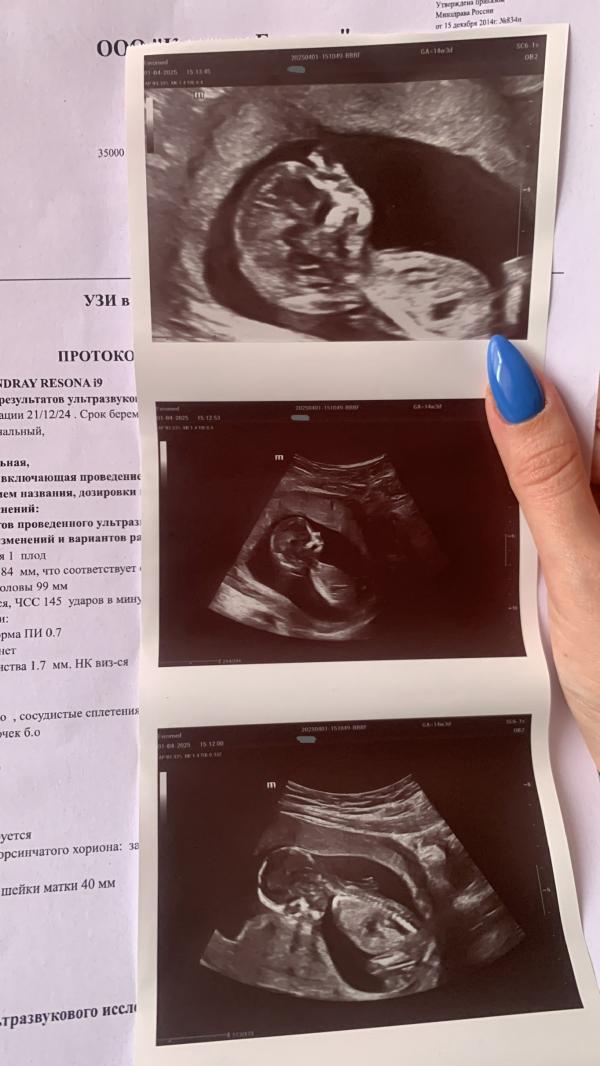

фото сегодняшнего скрининга и последняя фотосессия на узи, где рукой врача написан срок.